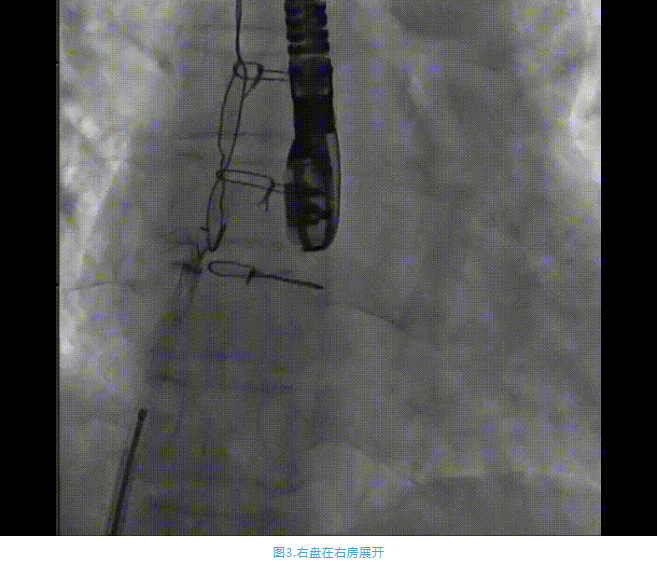

術中首先在局麻下穿刺股動脈、股靜脈,完成心導管檢查評估后轉為全麻,在食道超聲引導下穿刺房間隔,穿刺成功后將加硬導絲送入左上肺靜脈建立軌道,根據患者病情行球囊預擴張后植入6mm孔徑房間隔造孔支架,經透視及食道超聲評估支架左右盤展開良好,夾持于房間隔兩側,固定穩定、位置良好,食道彩超顯示房水平右向左為主分流,分流孔直徑符合預期大小,心導管檢查評估達到預期效果,釋放造孔支架。術后12h患者下床活動,恢復順利,擬于近日完善術后評估后出院。